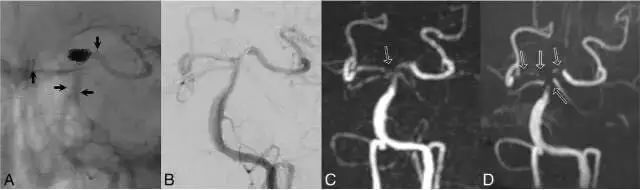

图2,病例2,75岁女性。A:Y型支架辅助的弹簧圈栓塞治疗,右侧PCA使用Neuroform支架,左侧PCA使用Enterprise支架,短箭头显示支架边缘;B. DSA图像显示阻塞完全;C. Silent MRA图像,在右侧PCA段可见中度信号丢失,显示阻塞完全;D. 同一天进行TOF-MRA检查,在基底动脉观察到中等强度的信号丢失,双侧PCA段可见完全的信号丢失(黑箭头),可见颈部残留(白箭头)